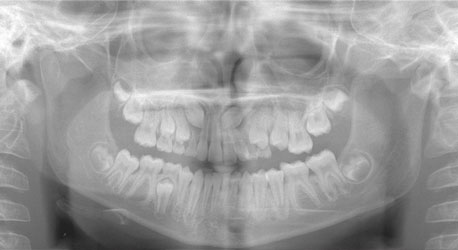

"Traditional" radiographs show a distorted image of impacted teeth, but it was the best we had.

The most recent radiographic innovation available is 3-D Cone Beam Technology, which are full head scans taking only 8.5 seconds. We can limit your radiographic exposure while providing all the images required in orthodontics plus a greater ability to pinpoint impacted teethevaluate airwayand aid in placement of implants. Cone Beam CT will likely be the standard of care in orthodontics in the near future. We are working with other offices when we need these special scans and we look forward to having this new technology in our office.